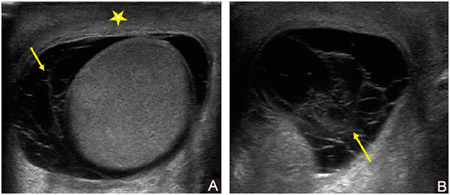

Ábra. Ultrahangos képalkotó hydrocele.

Ábra. Ultrahangos képalkotó haematocele. Testis körül egy folyadék, de a szerkezete nem homogén, az üreget osztva több partíciót.